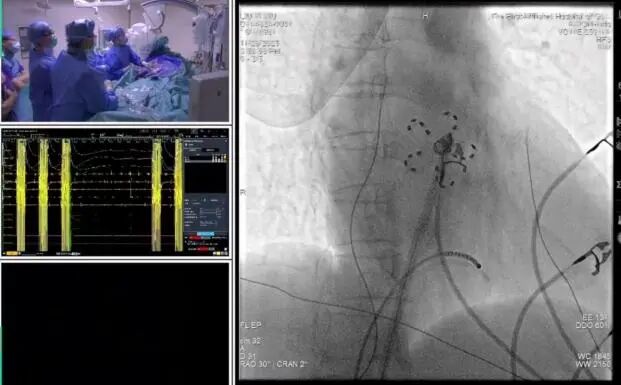

CASE 1:四川大学华西医院胡宏德教授、广州医科大学附属第一医院陈爱兰教授、韩敦正教授带来首台房颤脉冲消融+左心耳封堵(PFA+LAAC)一站式手术演示,将理论知识转化为临床实操,直观感受脉冲的高效性与无管麻醉的适配性。该患者为71岁女性,阵发性房颤合并房扑,存在高卒中和高出血风险,手术流程紧凑有序:同时完成铺巾消毒与喉罩麻醉(无管化),在 ICE 指导下开展股静脉穿刺、肺静脉隔离+后壁BOX消融+三峡部隔离+上腔静脉隔离及左心耳封堵。胡宏德教授总结:“这款导管贴靠好、效率高,配合无管麻醉实现全程无痛,患者术中体动少,既保障了消融线连续,封堵器位置准确,又让患者在舒适无痛中完成手术,大幅提升手术安全性与患者体验。”

Case 1:胡宏德、陈爱兰、韩敦正教授PFA+LAAC手术演示

CASE 2:宁波大学附属第一医院的储慧民教授、广州医科大学附属第一医院陈爱兰教授、李元庆教授、刘深荣教授带来第二台PFA+LAAC 一站式手术演示,全程以 ICE 为 “天眼”,无需依赖 X 线造影,40 分钟即完成肺静脉隔离与左心耳封堵,再次印证脉冲导管、超声技术与无管麻醉协同实现无痛治疗的优势。患者为73岁男性的阵发房颤患者,4 个月前因左心耳血流慢疑血栓,经充分抗凝后手术。储慧民教授在操作中强调 ICE 的重要性:“ICE 能清晰显示二尖瓣环、肺动脉、左心耳等解剖关系,脉冲导管贴靠时通过观察微泡情况判断贴合度 既提升消融有效性,又规避罕见并发症,配合无管麻醉让患者全程无痛,真正实现高效、精准、无痛的治疗目标。”

Case 2:储慧民、李元青、刘深荣教授PFA+LAAC手术演示